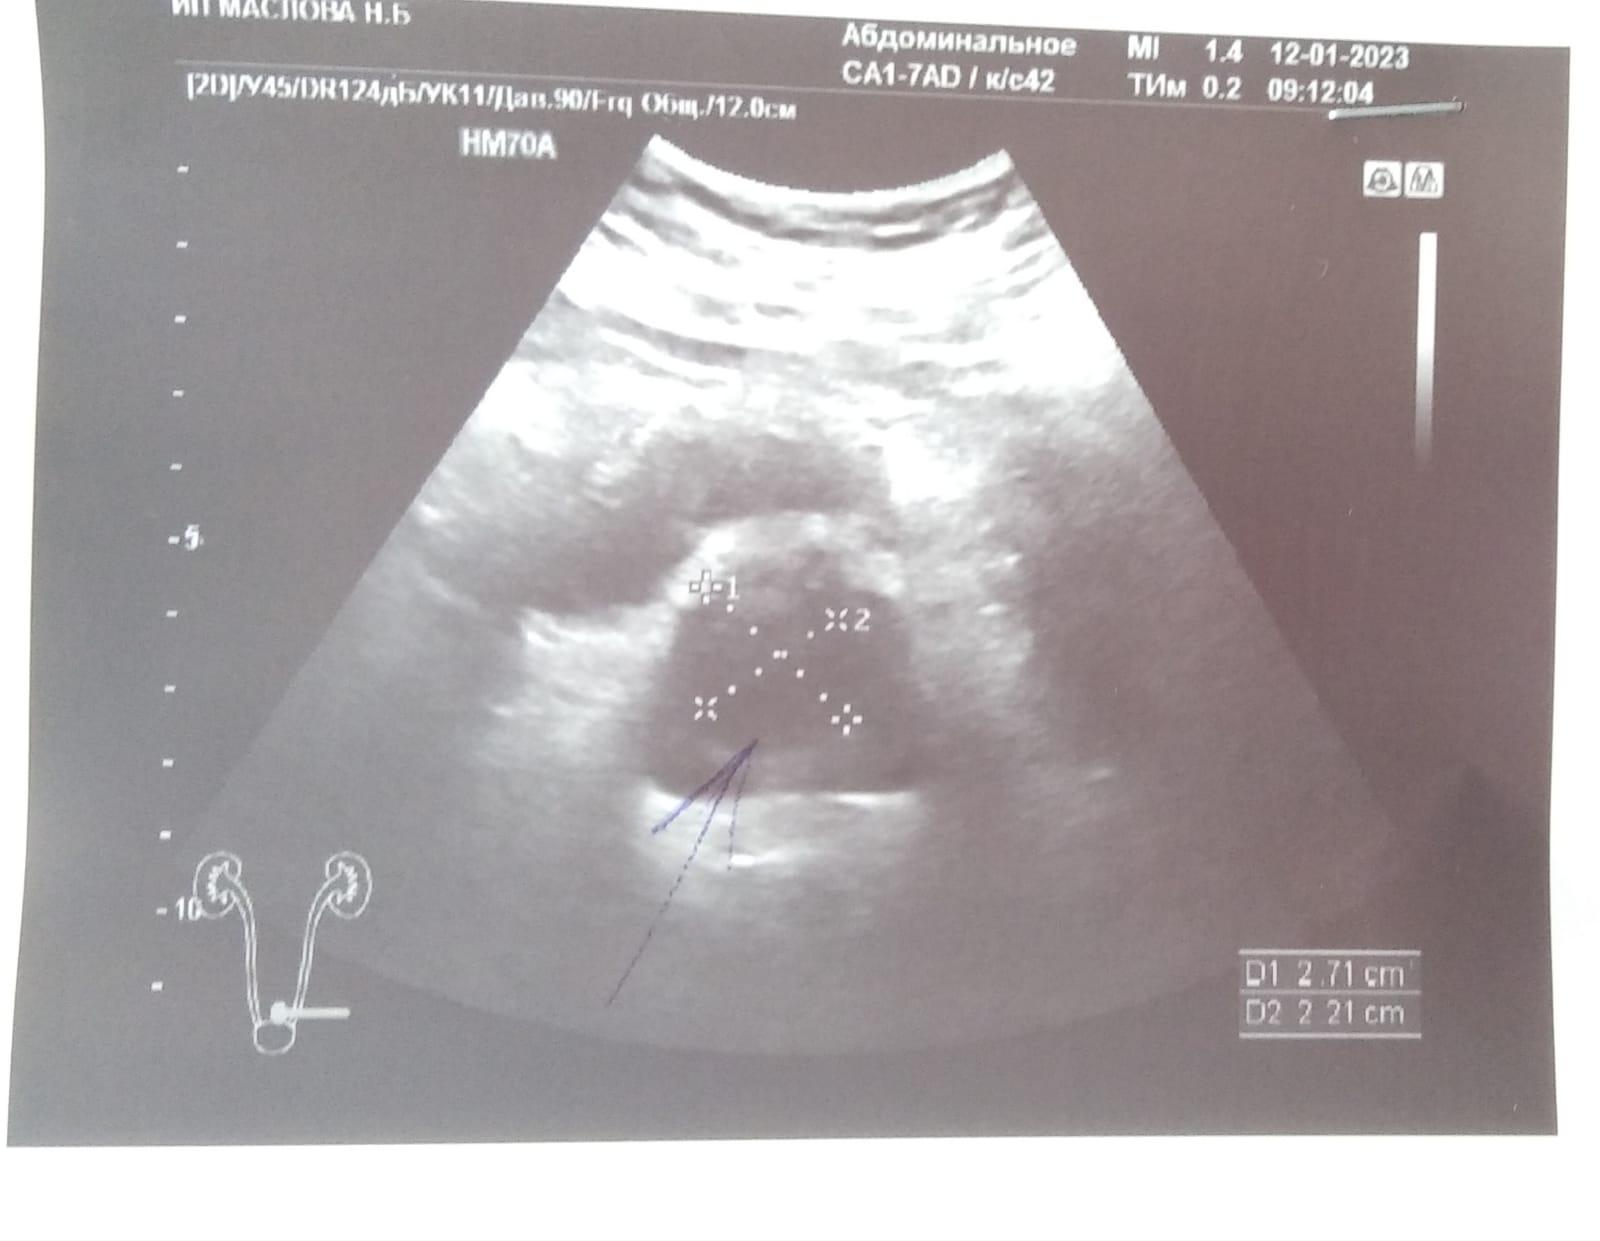

Здравствуйте.Сдал анализ ПСА,пришёл результат 12,свободный 0,8.остальные анализы кровь моча в норме.боли не беспокоют,сделали узи.результат прикрепляю.что это может быть.заранее спасибо!

Добрый день! Нужно выполнить МРТ малого таза, если в простате будут обнаружены подозрительные участки - нужно делать биопсию. В Барнауле можете обратиться к профессору Неймарку Борису Александровичу. Удачи.